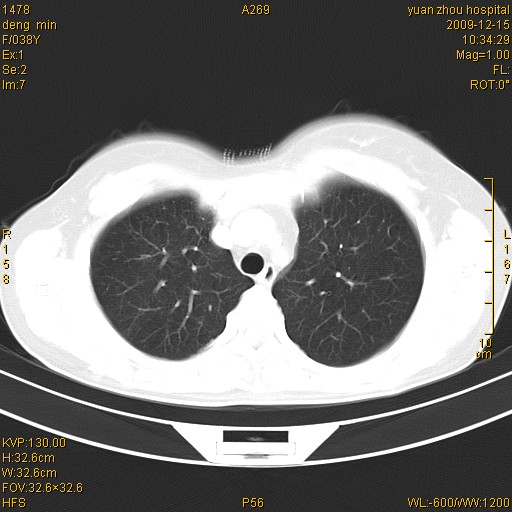

标题: CT23919:F38Y 咳嗽月余 [打印本页]

标题: CT23919:F38Y 咳嗽月余

支扩并感染

右肺中下叶、左肺上叶舌段及左肺下叶支气管扩张合并感染。